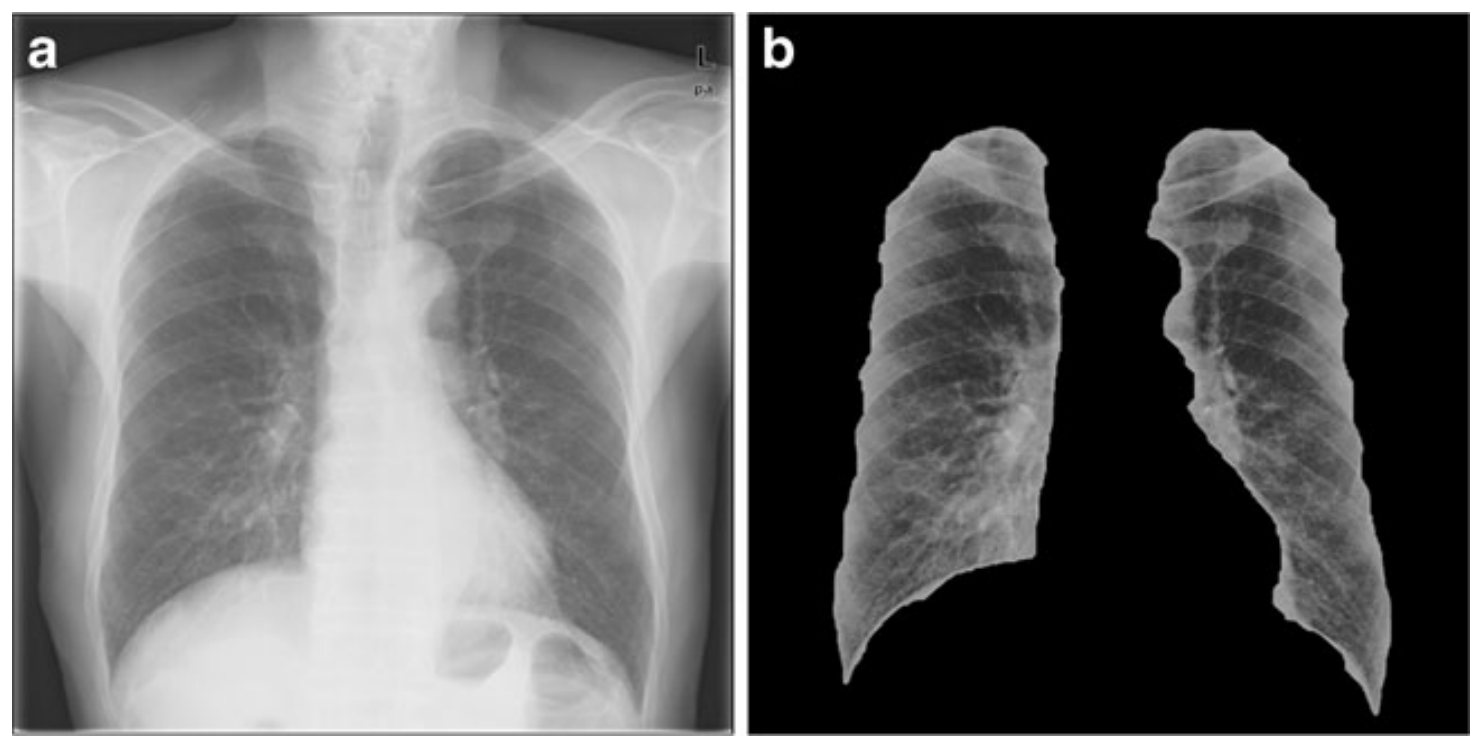

(Left) An original image of tennis players and a segmented version. (Right) A chest x-ray of a patient with pneumonia and a segmented version of the lungs in the image.